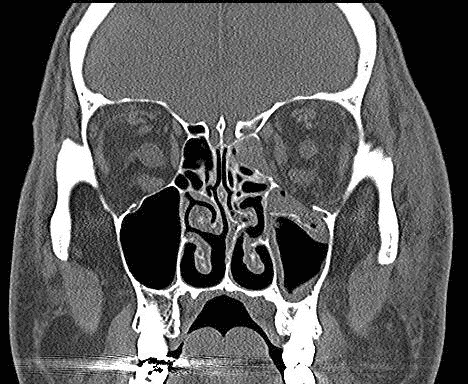

Зображення: орбітальний перелом

Зобр. 15. Комп’ютерна томограма, що демонструє переломи дна та медіальної стінки лівої орбіти.

Автор фотографії: Maj Brett Davies.